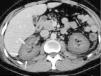

Presentamos un caso de FRA secundario a necrosis cortical bilateral en el contexto de una pancreatitis aguda grave (PAG). Se trata de un varón de 28 años de edad, sin antecedentes de interés a excepción de ser fumador. En abril de 2012 ingresa en la Unidad de Cuidados Intensivos (UCI) por pancreatitis aguda asociada a FRA anúrico. El paciente había acudido al Servicio de Urgencias 12h antes por cuadro de vómitos y dolor epigástrico con irradiación a hipocondrio derecho y región lumbar de 10h de evolución. A su llegada a Urgencias el paciente se encuentra hipotenso (93/34mmHg), con una frecuencia cardiaca de 55lpm, eupneico y saturando basalmente a 98%. En la exploración destaca dolor a la palpación en epigastrio e hipocondrio derechos. En la analítica destaca leucocitosis 19.100/μl, amilasa 787U/l, lipasa 11.606U/l, creatinina sérica 2,1mg/dl, urea 38mg/dl y lactato 2mmol/l, sin acidosis metabólica. La ecografía renal muestra riñones de tamaño normal con aumento de su ecogenicidad, indicativo de nefropatía médica, sin dilatación de la vía excretora. Con el diagnóstico de pancreatitis aguda y fracaso renal de probable origen prerrenal se inicia tratamiento con expansión volumétrica (3.000cc de cristaloides durante las primeras 12h), analgésicos, inhibidores de la bomba de protones y dieta absoluta. A las 12h de su llegada se avisa a la UCI por persistencia de anuria, ingresando en la Unidad. Se realiza TAC abdominal (con fase arterial y venosa tardía) con los siguientes hallazgos: páncreas globuloso con parénquima aparentemente conservado de densidad normal; aumento de densidad y trabeculación de la grasa peripancreática y líquido libre en el cuerpo y la cola del páncreas, ambas gotieras parietocólicas y pelvis menor, compatible con pancreatitis aguda; adecuada vascularización arterial y venosa, sin evidenciar afección en las arterias ni en las venas renales principales en el estudio arterial precoz y venoso portal; en el estudio venoso y tardío en ambos riñones se observa banda hipodensa, periférica, cortical, subcapsular, bilateral y simétrica que preserva la médula renal bilateral, hallazgos compatibles con NCA renal bilateral (fig. 1). Durante el ingreso en la UCI persiste en anuria, estando hemodinámicamente estable sin soporte vasoactivo y optimización del volumen intravascular, desarrollando acidosis metabólica (pH 7,30, HCO3 16,7mmol/l y exceso de bases −8,8mmol/l a pesar de la perfusión de bicarbonato), aumento progresivo de urea y creatinina (50 y 5,2mg/dl, respectivamente), e insuficiencia respiratoria secundaria a sobrecarga de volumen (pO2 55mmHg con aporte de oxígeno con mascarilla reservorio), requiriendo sesión de hemodiálisis con ultrafiltración de 2,5l a las 17h del ingreso, con mejoría clara de la situación respiratoria. Durante los 5 días de ingreso en la UCI persiste anúrico, requiriendo hemodiálisis diaria por uremia. Es trasladado a planta de Nefrología con el diagnóstico de PAG según la clasificación de Atlanta5 (Marshall modificado 9), y FRA anúrico secundario a probable NCA bilateral. Se realiza biopsia renal, que muestra un parénquima renal con una cortical con necrosis isquémica total; en las zonas más profundas se observa parénquima renal con cambios de necrosis tubular aguda, edema e inflamación intersticial, resultado que confirma el diagnóstico clínico de necrosis cortical o isquémica (fig. 2). Al recibir el alta hospitalaria se encuentra en situación de enfermedad renal crónica estadio 5, estando inicialmente en programa de hemodiálisis y posteriormente en programa de diálisis peritoneal. En marzo de 2014 recibe trasplante de donante vivo sin complicaciones. Al año del trasplante mantiene injerto normofuncionante con creatinina sérica de 1,46mg/dl y urea de 70mg/dl. Desde el punto de vista digestivo, en mayo de 2013 se realiza colecistectomía por episodios repetidos de pancreatitis aguda (octubre de 2012 y mayo de 2013) secundaria a microlitiasis biliar, quedando asintomático tras la colecistectomía.

El FRA aparece en el 3-8% de los pacientes con PAG, siendo un factor independiente de mal pronóstico6. Esta complicación suele aparecer en el seno de fracaso multiorgánico, siendo excepcional que ocurra en ausencia de fracaso respiratorio secundario a síndrome de distrés respiratorio agudo. En la inmensa mayoría de los casos se atribuye a necrosis tubular aguda como resultado de hipovolemia, respuesta inflamatoria sistémica con o sin infección sobreañadida y/o coagulación intravascular, siendo excepcional que se deba a NCA. Esta última se produce como consecuencia de una isquemia cortical tras la obstrucción de las arteriolas que irrigan la corteza renal. Dado que la necrosis de la corteza renal suele ser extensa y bilateral, se desarrolla insuficiencia renal aguda oligoanúrica. El diagnóstico de la NCA puede demostrarse por técnicas de imagen como la TAC, como ocurrió en nuestro caso, o la resonancia magnética nuclear, aunque es preciso la biopsia renal para su confirmación4,6,7. La gravedad de esta entidad radica en que el daño es permanente y, por tanto, la pérdida de la función renal es irreversible4. El único tratamiento a medio y largo plazo es la diálisis permanente y/o el trasplante renal.